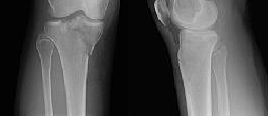

**CLINICAL SITUATION**

Figures 1 and 2 are the radiographs of a 35-year-old man who is brought into the emergency department after a motor vehicle collision. He is complaining of isolated knee pain. Examination reveals swelling, blood filled blisters, popliteal ecchymosis, joint line pain, and limited knee joint motion. His pulses and sensation are normal.

This knee injury is best described as a

Initial surgical management should consist of

Figures 3 through 8 are the axial and sagittal CT scan sections of the injury. Intra-operative patient positioning for definitive fixation should be

The surgical approach for definitive reduction and stabilization of this pattern is